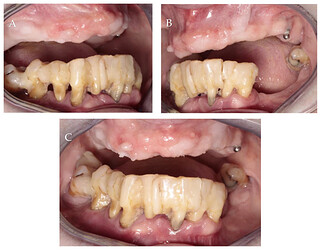

In this case, a 65-year-old female with generalized periodontitis, stage IV grade C and very poor oral hygiene came for treatment and rehabilitation of the lower jaw. It concluded that: “There is insufficient knowledge in the literature regarding the correlation between inadequate KM and the occurrence of peri-implantitis. Further research in this area is needed, especially case–control studies, cohort studies and randomized clinical trials.”3

Case below by: Jankowski T, Jankowska A, Kazimierczak N, Kazimierczak W, Janiszewska-Olszowska J. [The Significance of Keratinized Mucosa in Implant Therapy: Narrative Literature Review and Case Report Presentation.](The Significance of Keratinized Mucosa in Implant Therapy: Narrative Literature Review and Case Report Presentation - PMC

Initial intraoral photographs: (A) right lateral view; (B) left lateral view; (C) frontal view.